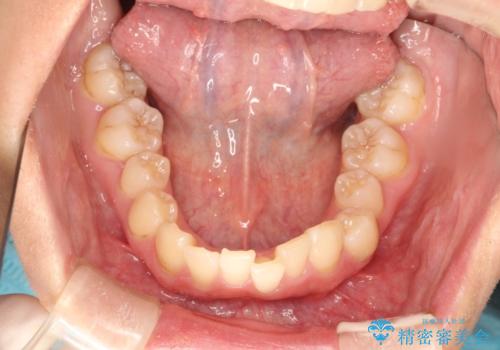

- 初診時には上顎前歯の突出、前歯部の深いかみ合わせ、叢生が見られる状態でした。

インビザラインにて不正咬合の原因除去を行うシミュレーションを念入りに制作の上、治療を行いました。